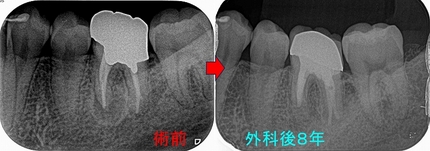

レントゲン

2026 EEdental MIH (1).jpg

かなり大きな虫歯があります。

患者さんにまず口腔外科で抜歯をしてもらい

術後3週間後に一度神経を残す方向でレジン充填を行い

痛みなどが出てしまったら、後で神経を取る処置を行なうと説明

2026 EEdental MIH (2).jpg

特殊な削り方をしてレジン(プラスチック)を詰めました。

親知らずの影響か、セメント質の肥厚が見られました。

2026 EEdental MA.jpg

大きく削って神経取っても、見えない為に虫歯は残したまま・・・

ホントこの部位の虫歯の治療は知っている・知っていないで大きく差が出てしまいます(>。<)